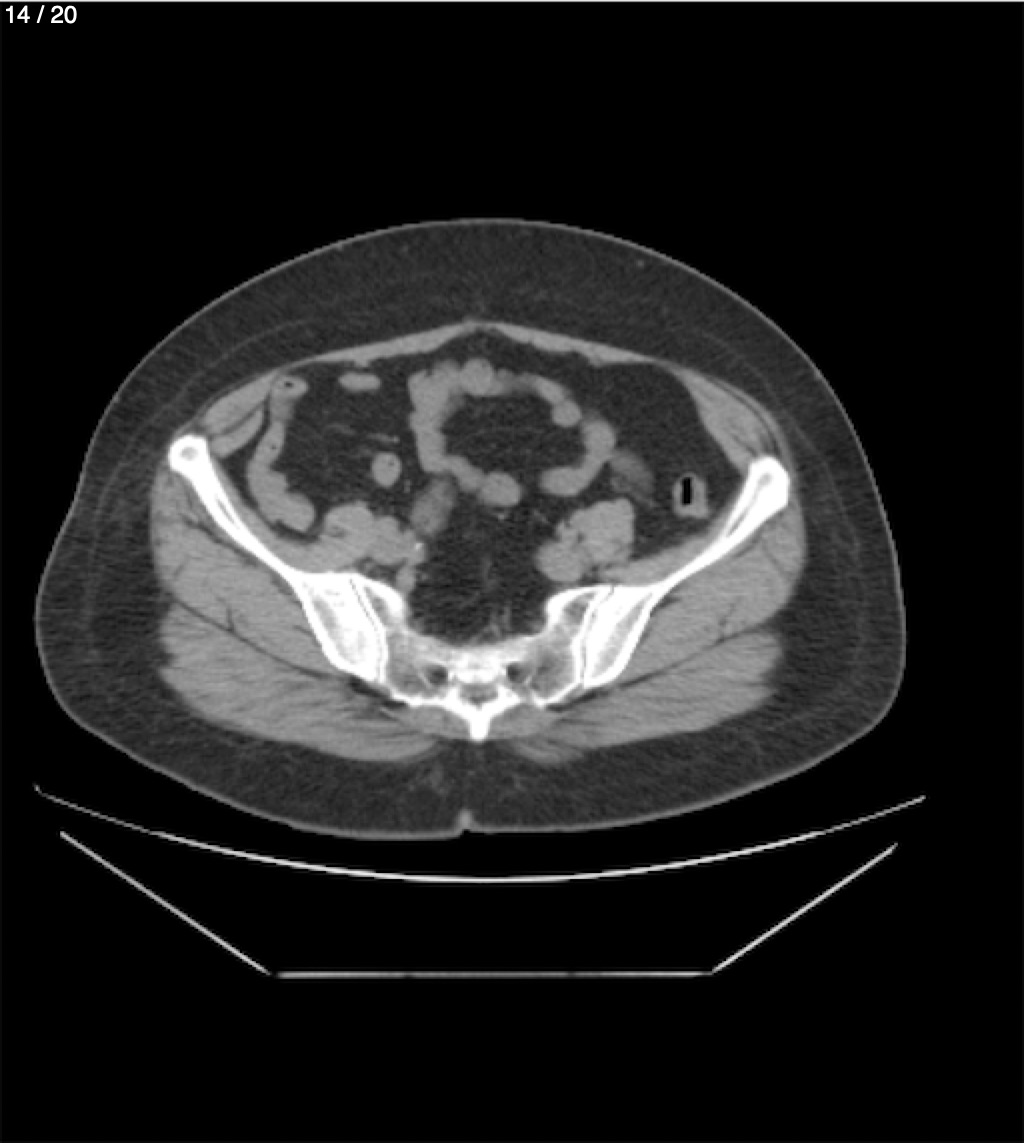

Maria Enrique Giron Dominguez63A - T.C Abdomen Simple